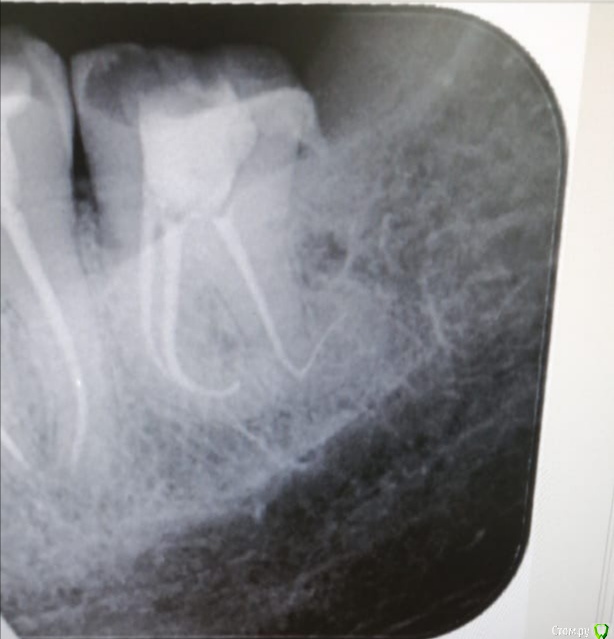

Паращук Роман Опубликовано 22 марта, 2020 Поделиться Опубликовано 22 марта, 2020 А меня вот недавно подвели эти ваши хваленые соко. Хотя на что надеялся, сам не знаю )) IMG_20200321_085701.jpgну пачка 06.02,пачка 08.02,пачка 10.02,тройка соко 15.03,тройка 20.04 и бинго.))))Дистальный очень сложный. Ссылка на комментарий

Бардо Опубликовано 22 марта, 2020 Поделиться Опубликовано 22 марта, 2020 ну пачка 06.02,пачка 08.02,пачка 10.02,тройка соко 15.03,тройка 20.04 и бинго.)))) Ну я до изгиба 25.06 поработал, потом 10 sc plus туда-обратно, потом перекрестился, 15 sc plus, но уже только туда ). В передних тоже сложно шло, но задний во рту такой без помощи фортуны мне, пожалуй, не взять Ссылка на комментарий